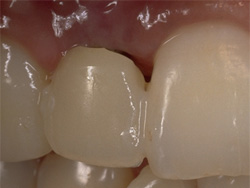

| インプラントの上のクラウンにより、あなたの咀嚼機能と自然な風貌が回復するでしょう。 |

| 失った部分にインプラントを1本埋入します。従来は健全な両隣の歯を削ってブリッジを用いて治療していましたが、インプラントを用いると健全な歯を削ることなく治療を行うことが出来ます。 |